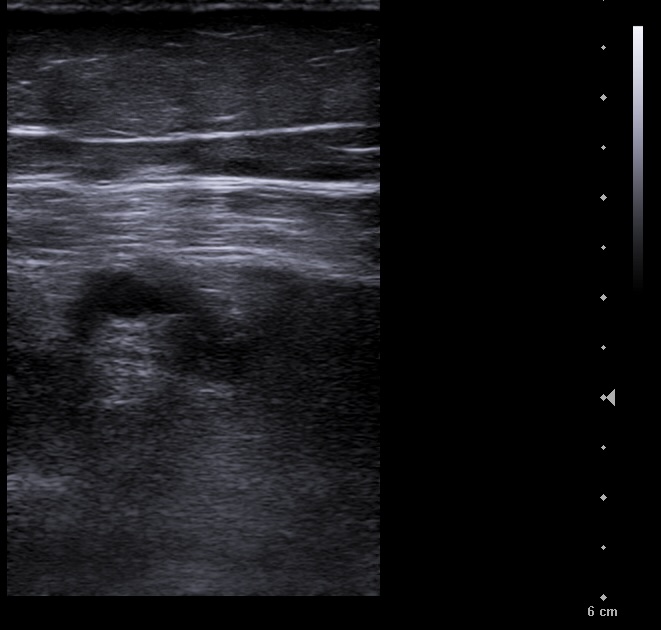

Vena poplitea no compresible, con material ecogénico en su interior y ausencia de flujo con Doppler color.